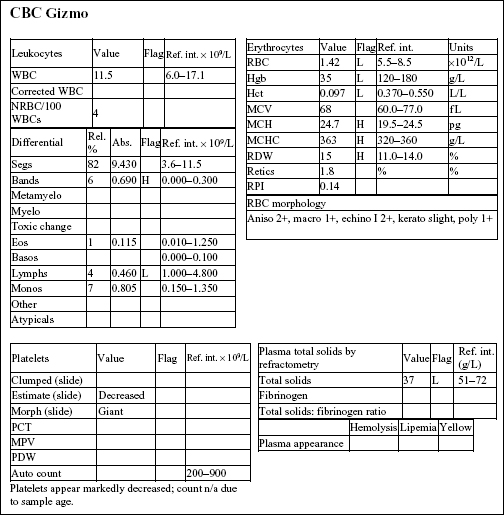

GIZMO, a 8-month old M Poodle dog, was presented in shock with white mucous membranes.

The Hct, Hgb, and RBC count are all severely decreased. Anisocytosis at 2+ and macrocytosis and polychromasia at 1+ could indicate mild/early regeneration, although the reticulocyte count and RPI do not support regeneration. Severe hypoproteinemia and severe anemia suggest acute blood loss. Platelet numbers are decreased, although an absolute platelet count is not available. Severe hemorrhage, internal or external, can result in significant platelet loss. Absolute numbers are not expected to become <80 × 109/L as a result of acute hemorrhage. Leukocyte numbers are within reference limits; however, there is a mild left shift and moderate lymphopenia. Given the state of shock in which the animal was presented, these leukogram changes could be entirely due to stress.

• Gizmo had ingested a rodenticide that contained a vitamin K antagonist. The dog had been bleeding into his chest cavity. Sufficient time had lapsed for low-protein interstitial fluid to move into the intravascular space in an attempt to correct the hypotension. Acute blood loss, whether internal or external, is typically accompanied by hypoproteinemia. Indications of regeneration should start to appear within 2–3 days in the dog.